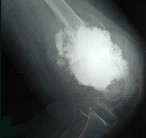

- 单项选择题女,10岁, 左大腿疼痛,夜间加重, 肿胀明显,请结合影像图像, 最可能的诊断为 ( )

A、骨化性肌炎

B、成骨性骨转移

C、化脓性骨髓炎

D、骨肉瘤

E、以上都不正确